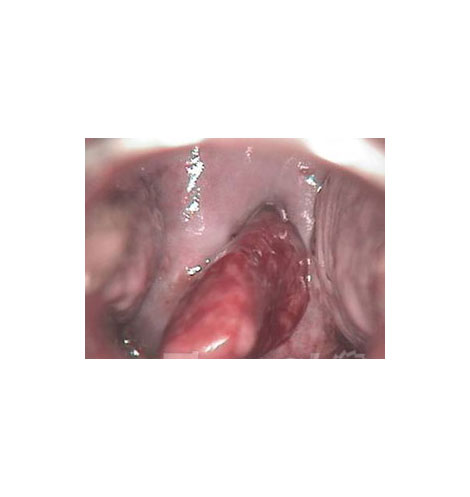

宫颈息肉实拍